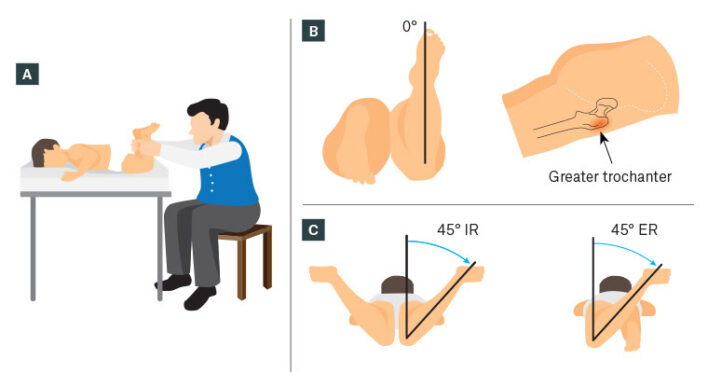

Xoay ở háng (đùi) thường được đánh giá với bệnh nhi ở tư thế nằm sấp, háng duỗi và gối gập đến 90°. Đánh giá tầm xoay trong và xoay ngoài của khớp háng. Gia tăng xoay trong khớp háng biểu hiện vặn trước của xương đùi, ngược lại tăng xoay ngoài có thể là biểu hiện của vặn sau và đụng chạm xương đùi – ổ cối. Để xác định mức vặn ra trước của xương đùi có thể đánh giá test Craig: đo góc giữa xương chày và trục đứng dọc vuông góc với mặt giường. Góc này ở người bình thường khoảng 15 độ.

Xoay của xương chày thể hiện qua mối tương quan giữa đường liên hai mắt cá (transmalleolar axis) với với trục dọc của đùi. Có thể đánh giá điều này thông qua đo trục đùi -bàn chân (trục đùi- bàn chân cũng thay đổi khi có sự xoay của phần bàn chân sau, hind foot). Trẻ nhũ nhi thường có góc đùi- bàn chân xoay trong 5° và chuyển sang xoay ngoài khoảng 10° lúc trẻ 8 tuổi. Cũng có thể đo góc đường giữa trục xương đùi với đường liên mắt cá.

Kết hợp đánh giá mức độ xoay ở các phân đoạn và so sánh với các giá trị bình thường dự kiến cho mỗi đoạn cho phép nhận biết và chẩn đoán sớm các bất thường về xoay ở trẻ đang lớn.